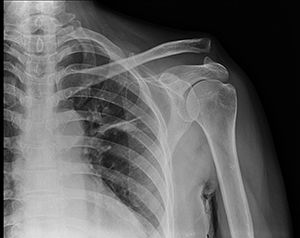

Рентген ключицы

Рентген ключицы — одна из наиболее часто применяемых диагностических методик, основанная на использовании рентгеновских лучей. Она позволяет получить данные о состоянии костной ткани ключи, выявить её переломы, увидеть новообразования, а также врождённые дефекты и аномалии строения.

Рентгенография ключичной кости позволяет визуализировать костную ткань. Нередко проводят профилактический рентген здоровой ключицы, который позволяет выявить заболевания плечевого пояса на ранней стадии развития. Такой подход рекомендуют пациентам, которые регулярно подвергаются физическим нагрузкам (к примеру, профессиональным борцам). Диагностические исследования позволяют выявить:

• Трещины и переломы кости;

• Остеофиты и другие новообразования;

• Врождённые дефекты;

• Аномалии строения и развития.

Снимки здоровой ключи должны демонстрировать кость правильной формы, размеры которой соответствуют возрасту пациента. Изображение костей должно быть максимально чётким, структура — однородной, затемнений быть не должно.